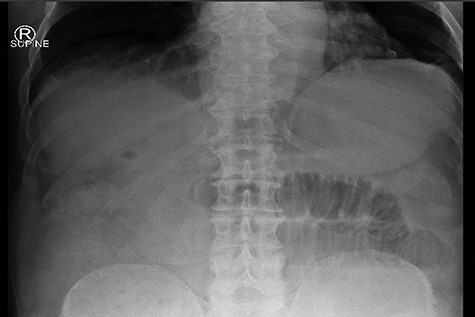

An 81-year-old gentleman presented to the emergency department with a 2-day history of vomiting, central abdominal pain and distension. He had no prior abdominal surgeries, but was waiting for an elective cholecystectomy for chronic cholecystitis. On examination, his abdomen was distended, with mild central abdominal tenderness and no evidence of umbilical or groin hernia. Blood tests were unremarkable except for mild acute kidney injury secondary to dehydration. His plain abdominal X-ray showed dilated small bowel loops (Fig. 1), consistent with a developed SBO. Given the scenario of SBO in a virgin abdomen, a computed tomography (CT) of abdomen was performed, which confirmed the diagnosis of SBO with the transition point being at close proximity to the gallbladder.